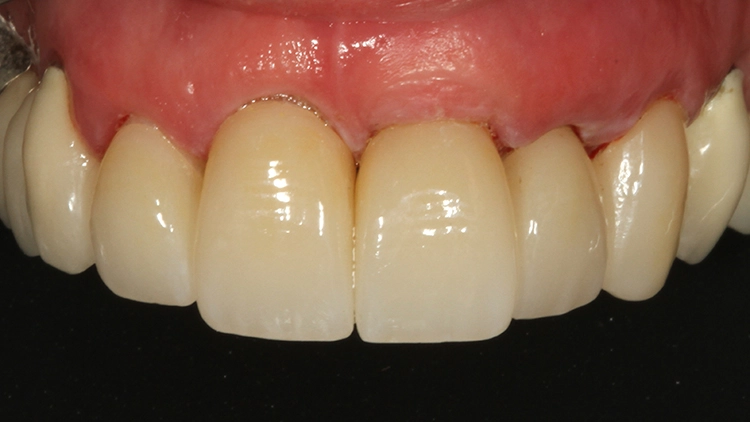

Bis zur definitiven prothetischen Versorgung sollte aufgrund etwaiger Gewebeveränderungen 6 Monate gewartet werden. Nach dieser Wartezeit zeigte sich ein stabiles, rezidivfreies parodontalchirurgisches Behandlungsergebnis (Abb. 8 und 9).

Bei der jetzt anstehenden Teilkronen- bzw. Veneerversorgung der Zähne 12 bis 23 blieb zunächst die Frage des keramischen Restaurationsmaterials zu klären. Neben der bewährten und hochästhetischen glasbasierten Keramik [2,8,10,14–16] eignen sich heutzutage transluzente Zirkonoxidmaterialien hervorragend für die ästhetische Ausgestaltung von Frontzahnbereichen [11], da sie genauso gut verklebt werden können wie Glaskeramiken [9,23].

Gerade im Bereich parafunktional gefährdeter Areale punktet das gegenüber der klassischen Glaskeramik doch deutlich bruchfestere Vollzirkonmaterial. Da bei der Patientin bereits mehrfach Füllungen und Inzisalkanten frakturierten, fiel in diesem Fall die Materialauswahl auf ein hochtransluzentes, polychromes Vollzirkon (zolid fx multilayer, Amann Girrbach), welches mit Ceramotion ZR (Dentaurum) verblendet wurde. Hergestellt wurde die Arbeit (Abb. 10 und 11) im eigenen Meisterlabor durch ZTM Richard Bohrer.